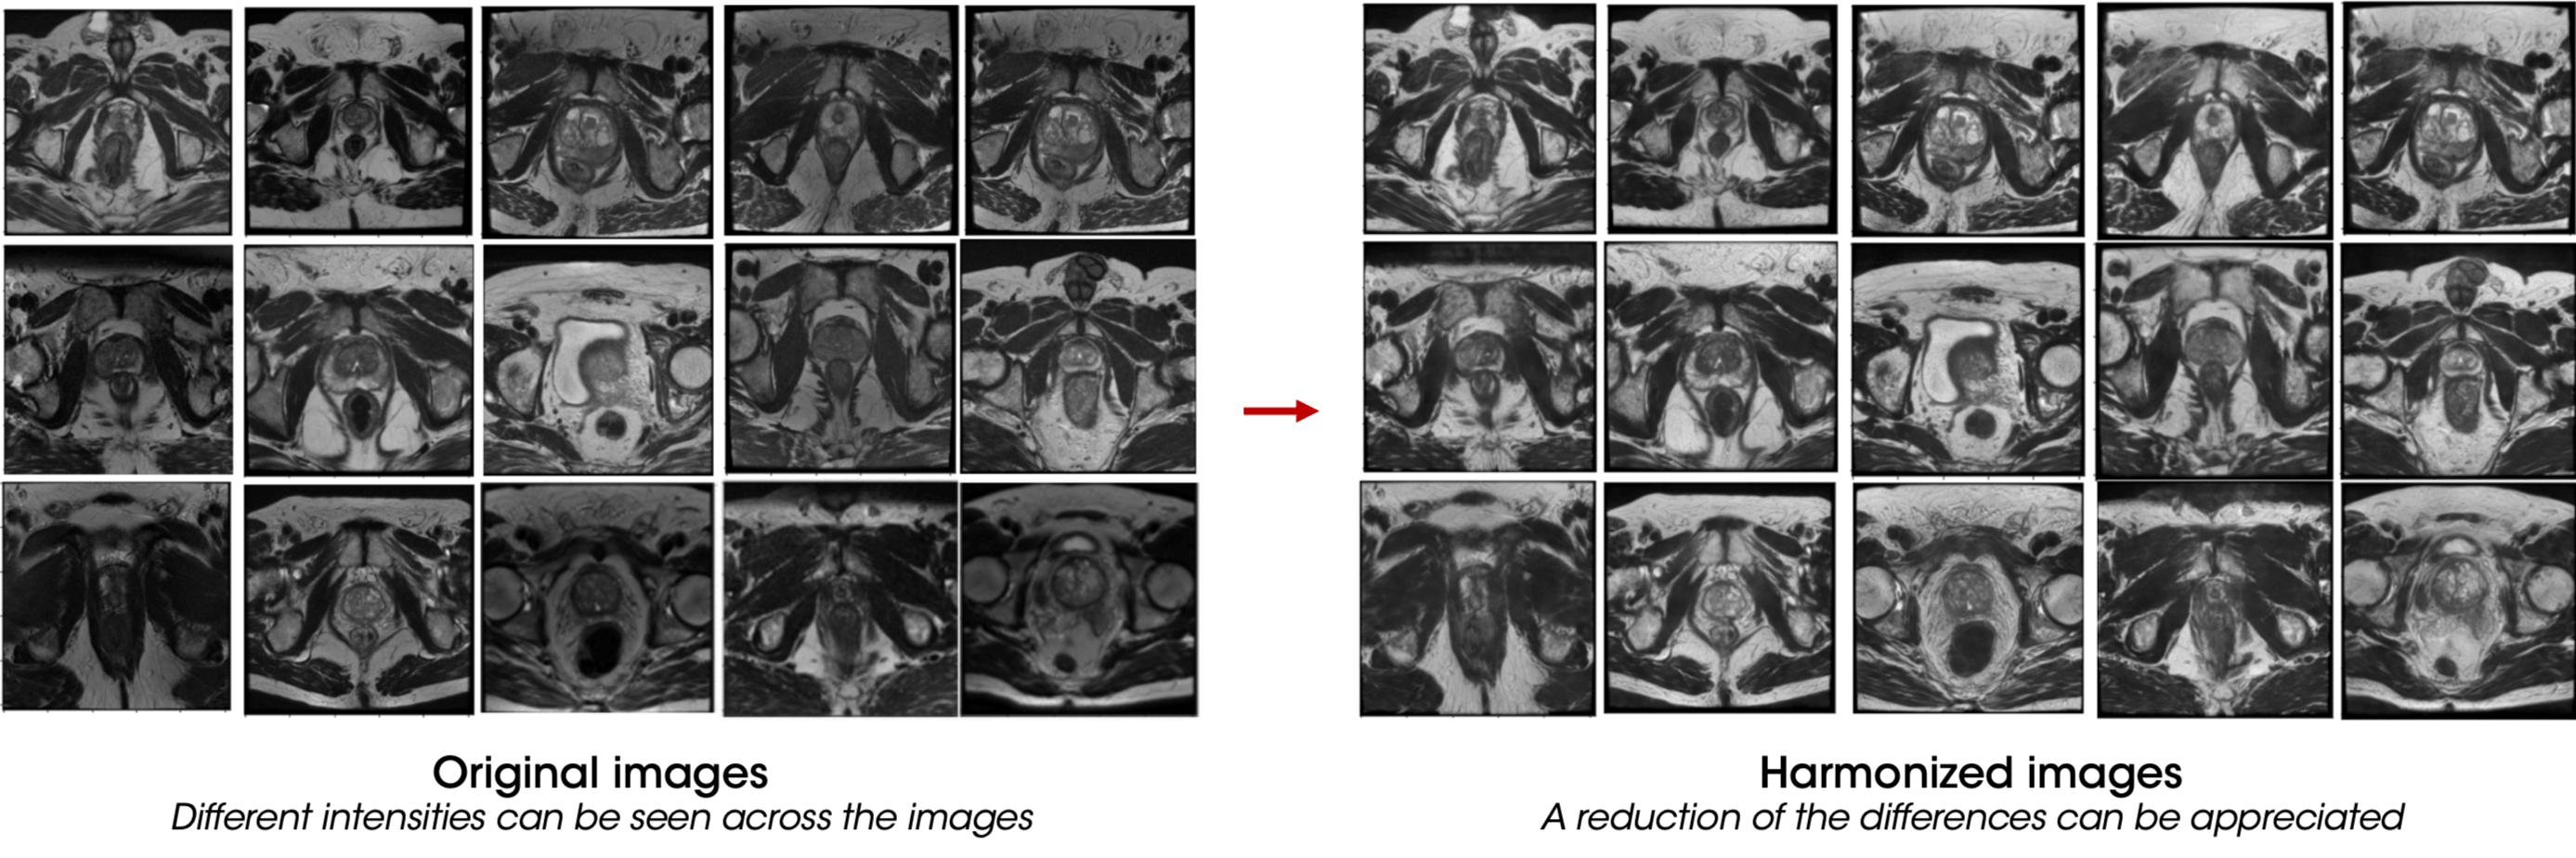

To build robust prognostic models, collecting data from various institutions is essential, considering as much variability as possible. However, the main challenge in multi-centric imaging studies lies in the heterogeneity of scanners and acquisition protocols. To address this limitation, harmonization tools are essential. AI in radiology has shown promising results in this field8, effectively reducing the variabilities commonly encountered in datasets acquired from different scanners.

- Data quality and diversity: One of the core benefits of AI in radiology is its reliance on vast, diverse datasets. Ensuring data quality, diversity, and standardization remains challenging, as medical images can vary significantly regarding acquisition techniques and quality. Even though a significant improvement has been made in AI-based harmonization techniques, the future of AI in radiology necessitates collaborative efforts to create comprehensive and standardized datasets for training AI algorithms effectively.